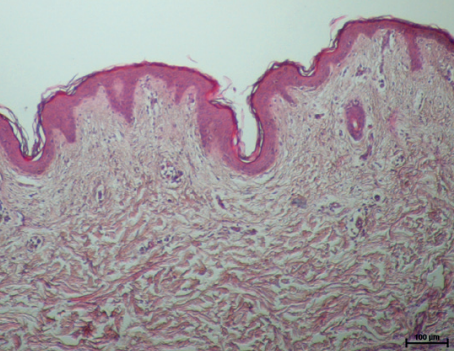

실제 온다 리프팅 시술 후 피부 진피의 콜라겐 변화를 확인한 조직학 사진입니다.

시술 전과 후를 비교해보면 콜라겐 생성을 통해 훨씬 치밀해진 피부층을 확인할 수 있죠.